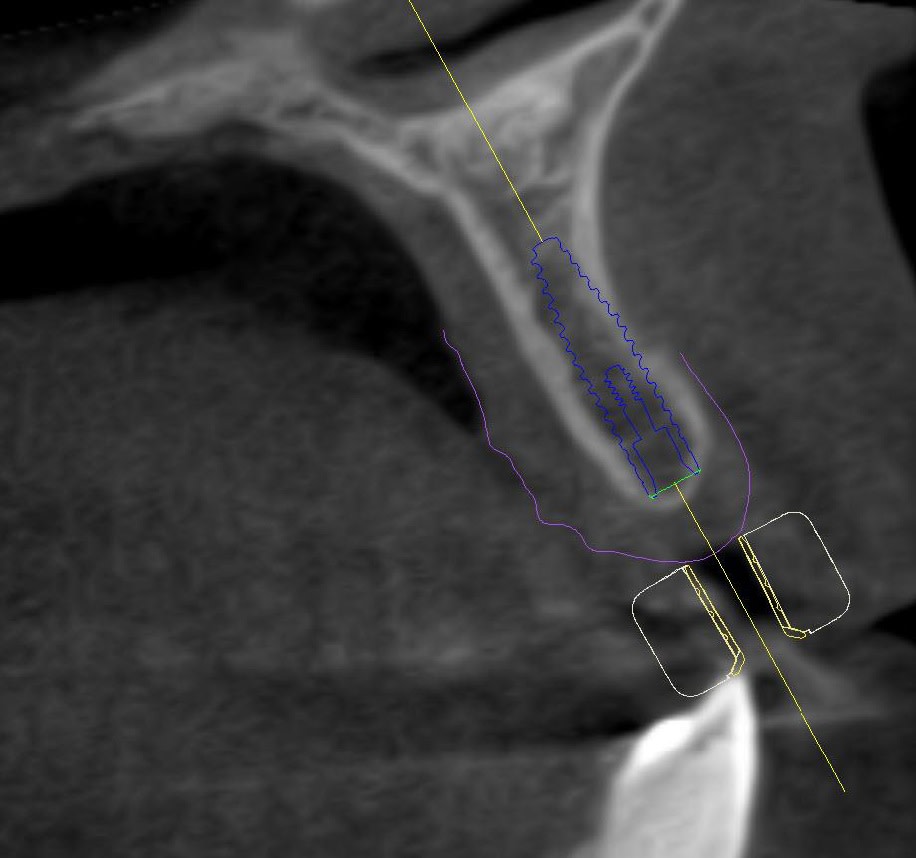

Upon completion of the orthodontic therapy, the gaps between the roots of the adjacent teeth and the crowns of the adjacent teeth were restored. The patient was showing very limited gap widths and unfavorable interradicular space conditions. Initial marginal bone thickness in the gaps was approximately 4.5 mm (Figure 3) with apical thinning (Figure 4 and Figure 5).

After discussing the treatment plan with the patient it was agreed upon that two small-diameter (2.9 mm) implants would be placed in positions 7 and 10, followed by fixed restorations. The position of the implants was carefully assessed using a cone-beam computed tomography (CBCT) technique (Figure 4 through Figure 6), and a 3D surgical drilling template was developed and printed to facilitate the drilling process (Figure 7 and Figure 8). Postoperative temporary prostheses were created to avoid gingival pressure and to secure the position stability of the adjacent teeth (Figure 9).

The patient was prescribed with antibiotic (2x 600-mg Clindamycin for 7 days) and anti-inflammatory (Ibuprofen 400 mg) therapy. Exact positioning of implants was further controlled and confirmed using ultra low-dose CBCT technique (Figure 12 and Figure 13).